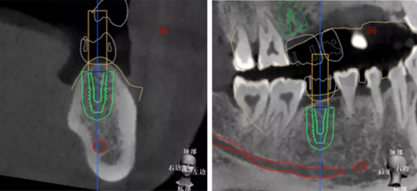

查看種植體螺絲通道穿出虛擬修復(fù)體的位置。

查看種植體在牙槽嵴頂穿出位置。

種植規(guī)劃與術(shù)后CBCT影像對(duì)比